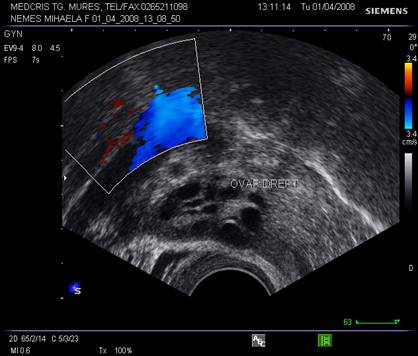

examen Doppler tumoral sau al organelor genitale interne,

Ovarele. Sectiunea longitudinala directa, spre peretele lateral pelvin, la ecografia transvaginala, pune in evidenta ovarele cu forma elipsoidala. Acestea au structura ecografica relativ slab ecogena, in apropierea si sub vasele iliace.[5]

vascularizatie crescuta periferica la ecoDoppler